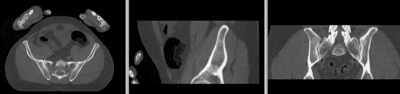

v3.6.3 Slicer3-6Announcement-v1.png Slicer Registration Library Case 44: Visible Human Pelvis CT

Input

this is the main fixed reference image. All images are ev. aligned into this space lleft this is the moving image

baseline image follow-up

This dataset contains CT of the visible human male and female pelvis. This serves as a test example for exploring non-rigid registration for inter-subject comparison from CT.

• fixed: CT , 0.6 x 0.6 x 0.40 mm voxel size, axial; 292 x 292 x 91 unsigned short image

• moving: CT , 0.6 x 0.6 x 0.40 mm voxel size, axial; 512 x 512 x 107 unsigned short image